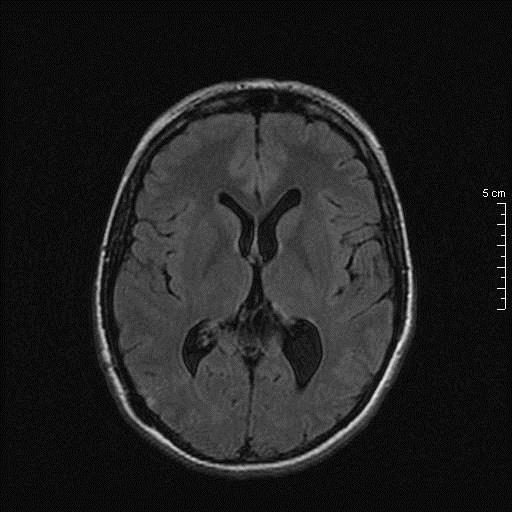

Η ασθενής κινητοποιήθηκε πλήρως την πρώτη μετεγχειρητική ημέρα χωρίς νέο εστιακό νευρολογικό έλλειμμα και έλαβε εξιτήριο την επομένη.

Μετεγχειρητικός απεικονιστικός έλεγχος